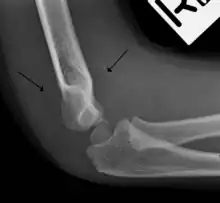

The fat pad sign, also known as the sail sign, is a potential finding on elbow radiography which suggests a fracture of one or more bones at the elbow. It is may indicate an occult fracture that is not directly visible. Its name derives from the fact that it has the shape of a spinnaker (sail).[1] It is caused by displacement of the fat pad around the elbow joint. Both anterior and posterior fat pad signs exist, and both can be found on the same X-ray.

In children, a posterior fat pad sign suggests a condylar fracture of the humerus. In adults it suggests a radial head fracture.

The fat pad sign is invaluable in assessing for the presence of an intra-articular fracture of the elbow. An anterior fat pad is often normal. However a posterior fat pad seen on a lateral x-ray of the elbow is always abnormal. The patient will be unable to flex their elbow and requires orthopaedic input.[2]

The posterior fat pad is normally pressed in the olecranon fossa by the triceps tendon, and hence invisible on lateral radiograph of the elbow.[3] When there is a fracture of the distal humerus, or other pathology involving the elbow joint, inflammation develops around the synovial membrane forcing the fat pad out of its normal physiologic resting place. This is visible as the "posterior fat pad sign" and is often the only visible marker of a fracture, particularly in the pediatrics population.